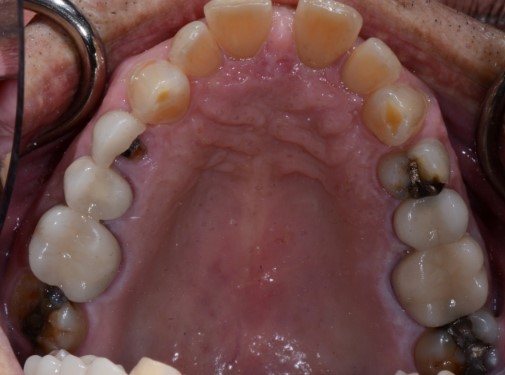

How many patients have you seen who continually break teeth? Some patients break multiple teeth within a short time frame, often, caused by cuspal interferences when the mandible is moving side to side or forward. Assess how many crowns a patient already has and ask them why the crowns were placed. Gather information from their past crown history to gain a respect for the system you’re about to put the next crown into. Every time we do a crown on a single fractured tooth, we’re placing our new crown right back into the system that broke it in the first place. Set a number in your mind of how many teeth a patient needs to break before we’re comfortable discussing balance.

Tooth wear

Like pain, tooth wear can be multifactorial, but after a thorough history and clinical exam, we should be able to sort out tooth wear caused by extrinsic forces (acid erosion) vs. tooth wear caused by tooth-to-tooth contact (attrition).

Cases of attrition are often present in the unbalanced environment where a patient is naturally balancing themselves. The question here: What is the long-term consequence? Clinically, this can show anywhere from one canine with a flat incisal edge to an entire arch of teeth with completely flattened cusp tips. The worn area of one tooth or arch will have an equal and opposite pattern of wear in the other tooth or arch.